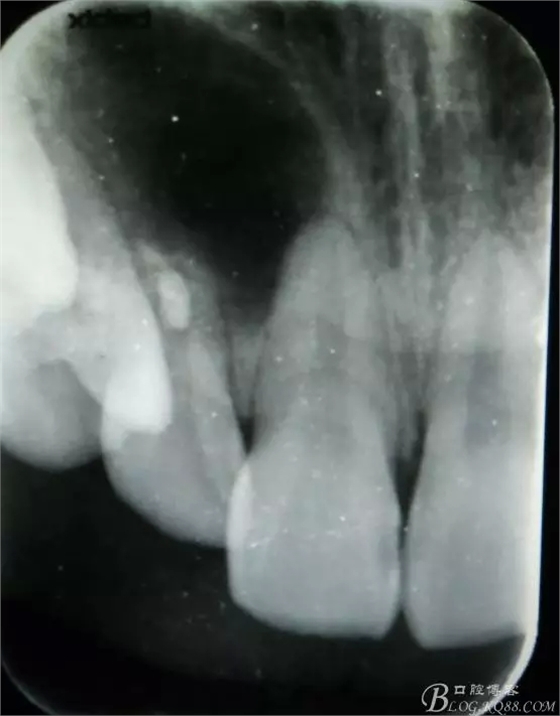

病例資料: 患者、柴xx、女、16歲。??茩z查及病歷如下圖: 患者同意我院正畸科建議,遂轉(zhuǎn)診倒外科。術(shù)前簽知情同意書。 治療過程: 圖1.術(shù)前的CBCT檢查:13阻生,疑為含牙囊腫。縱剖面顯示12牙根吸收至根尖1/3。 圖2.局部麻醉下 。行唇側(cè)弧形切口,12松動不到1°。 圖3.翻瓣、暴露骨面。 圖4.去骨、 暴露13牙冠 圖5.去骨、逐漸顯露13。 圖7.拔除13. 圖8.摘除囊壁 圖9.必須完整剝離囊壁。 圖10.摘除囊壁后形成的骨腔 圖11.超聲骨刀12根尖倒預(yù)備 圖13. 消毒棉球骨腔內(nèi)隔濕血液,紙尖干燥倒預(yù)備好的根管 圖14. 紙尖無血即可 圖15。MTA倒充填 圖16.骨腔填塞膠原蛋白海綿 圖17.拔除的13及摘除的囊壁 圖18.縫合 圖19.術(shù)后x線根尖片影像:MTA封閉根尖